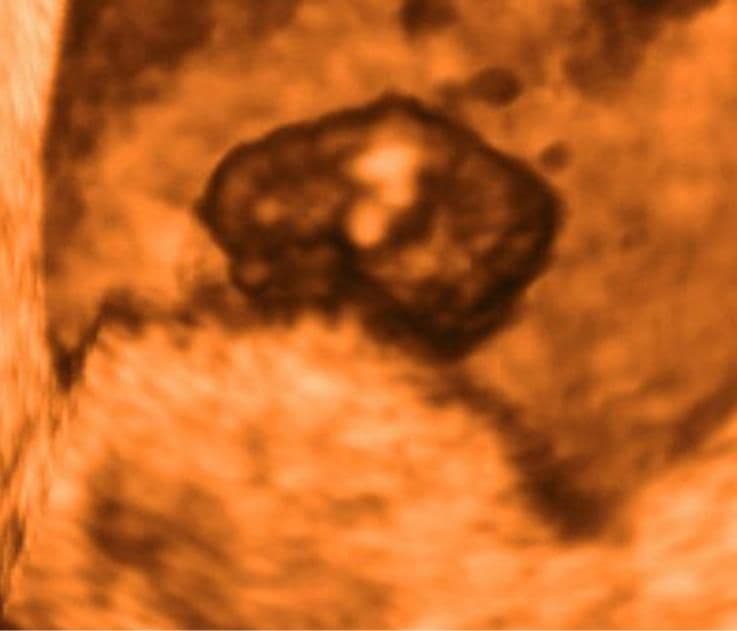

This ultrasound scan of the baby in side view shows that the head (at top) is relatively large compared to the rest of the body. The lighter, elongated area at the centre of the baby’s darker body is an upper arm bud.